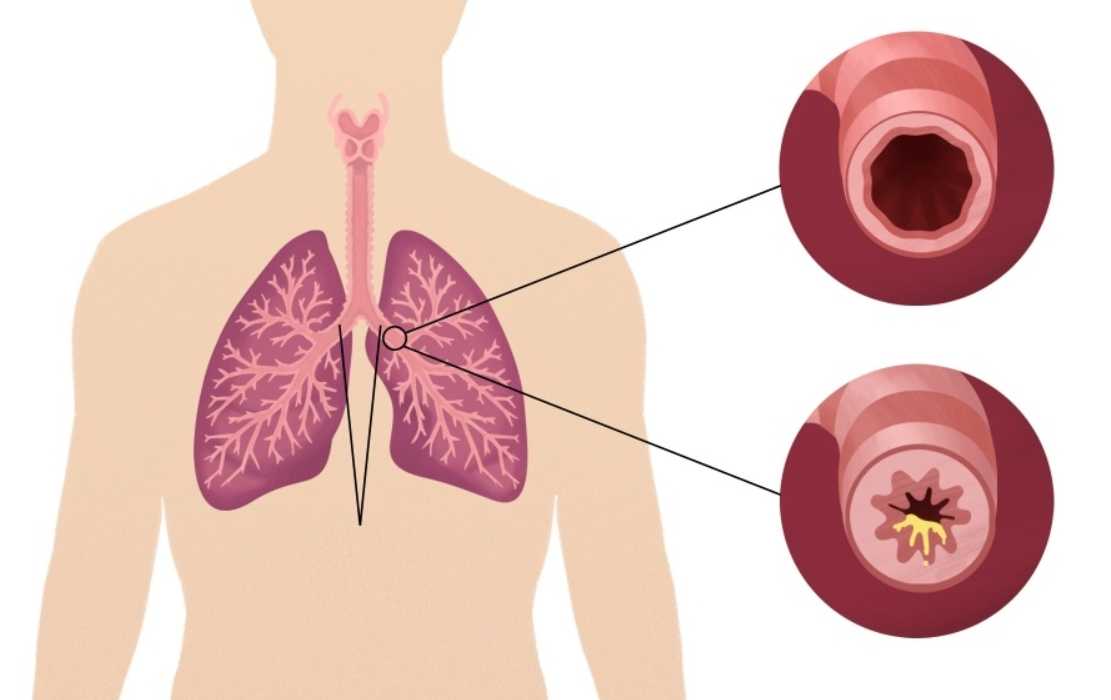

Бронхит – заболевание дыхательной системы, при котором происходят воспалительные процессы в бронхиальном дереве. Одни из основных признаков болезни — значительное повышение температуры тела и кашель. Но иногда бывает и бессимптомное течение бронхита. Как диагностировать его в этом случае и какие методы лечения использовать, узнайте далее.

Бронхи – очень чувствительная к различным воздействиям часть легких. Воспаление их тканей может развиться по разным причинам.